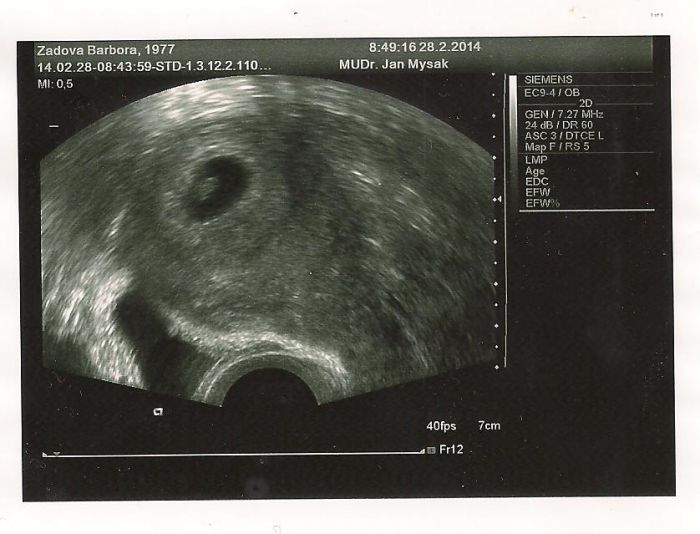

Ahoj Anito,kontrola proběhla v pořádku, miminku bije srdíčko a to je pro mě nejdůležitější :-). Je 9 mm velké, nebo spíš malé :-D. Jsem teď ještě víc šťastnější když jsem ho viděla. Taky se dočkáš kontroly, ale to čekání je hrozný, na další jdu 20.3. Mám taky báječného partnera, každý den mi na mail chodí co se ten den s miminkem dějě, nebo jak se vyvíjí, a každý den mu to čtu. Měla jsem poslední těhu před 11 lety, a teď si to snad užívím ještě víc, protože vim že je to poslední :-), ale moc chtěný stejně jako moje 2 děti. A musim se pochlubit fotkou i když je to zatim jen taková čmouha :-).